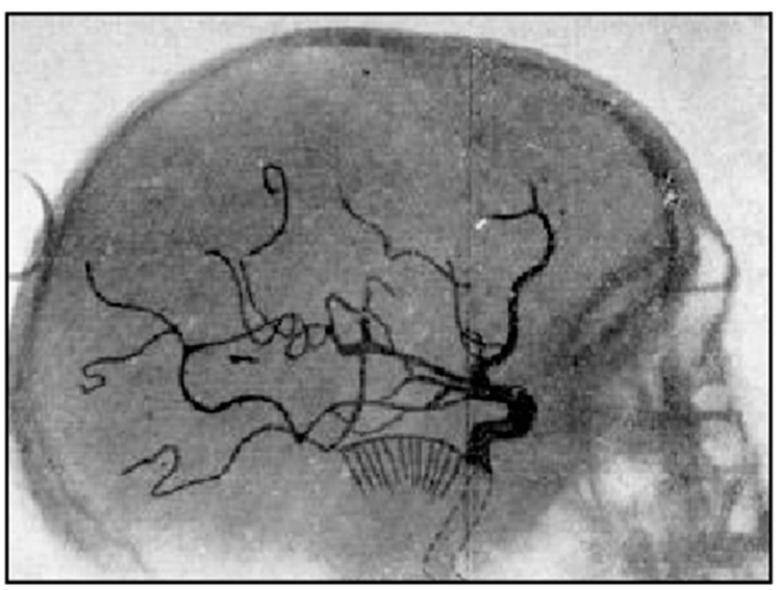

Ultra-high contrast (UHC) MRI describes forms of MRI in which little or no contrast is seen on conventional MRI images but very high contrast is seen with UHC techniques. One of these techniques uses the divided subtracted inversion recovery (dSIR) sequence, which, in modelling studies, can produce ten times the contrast of conventional inversion recovery (IR) sequences. When used in cases of mild traumatic brain injury (mTBI), the dSIR sequence frequently shows extensive abnormalities in white matter that appears normal when imaged with conventional T-fluid-attenuated IR (T-FLAIR) sequences. The changes are bilateral and symmetrical in white matter of the cerebral and cerebellar hemispheres. They partially spare the anterior and posterior central corpus callosum and peripheral white matter of the cerebral hemispheres and are described as the whiteout sign. In addition to mTBI, the whiteout sign has also been seen in methamphetamine use disorder and Grinker's myelinopathy (delayed post-hypoxic leukoencephalopathy) in the absence of abnormalities on T-FLAIR images, and is a central component of post-insult leukoencephalopathy syndromes. This paper describes the concept of ultra-high contrast MRI, the whiteout sign, the theory underlying the use of dSIR sequences and post-insult leukoencephalopathy syndromes.

超高对比(UHC)MRI 描述了这样一些 MRI 形式,在常规 MRI 图像上几乎没有或没有对比,但在 UHC 技术中可以看到非常高的对比。其中一种技术使用分裂相减反转恢复(dSIR)序列,在建模研究中,该序列可以产生比常规反转恢复(IR)序列高十倍的对比度。当用于轻度创伤性脑损伤(mTBI)时,dSIR 序列经常在白质中显示出广泛的异常,而在使用常规 T 液衰减反转恢复(T-FLAIR)序列成像时,白质看起来正常。这些变化在大脑和小脑半球的白质中是双侧对称的。它们部分保留了前中央和后中央胼胝体以及大脑半球的外周白质,被描述为“白化征”。除了 mTBI 之外,在没有 T-FLAIR 图像异常的情况下,该白化征也出现在苯丙胺使用障碍和 Grinker 髓鞘病(缺氧后迟发性白质脑病)中,是创伤后白质脑病综合征的一个核心组成部分。本文描述了超高对比 MRI、白化征、dSIR 序列使用的理论以及创伤后白质脑病综合征的概念。